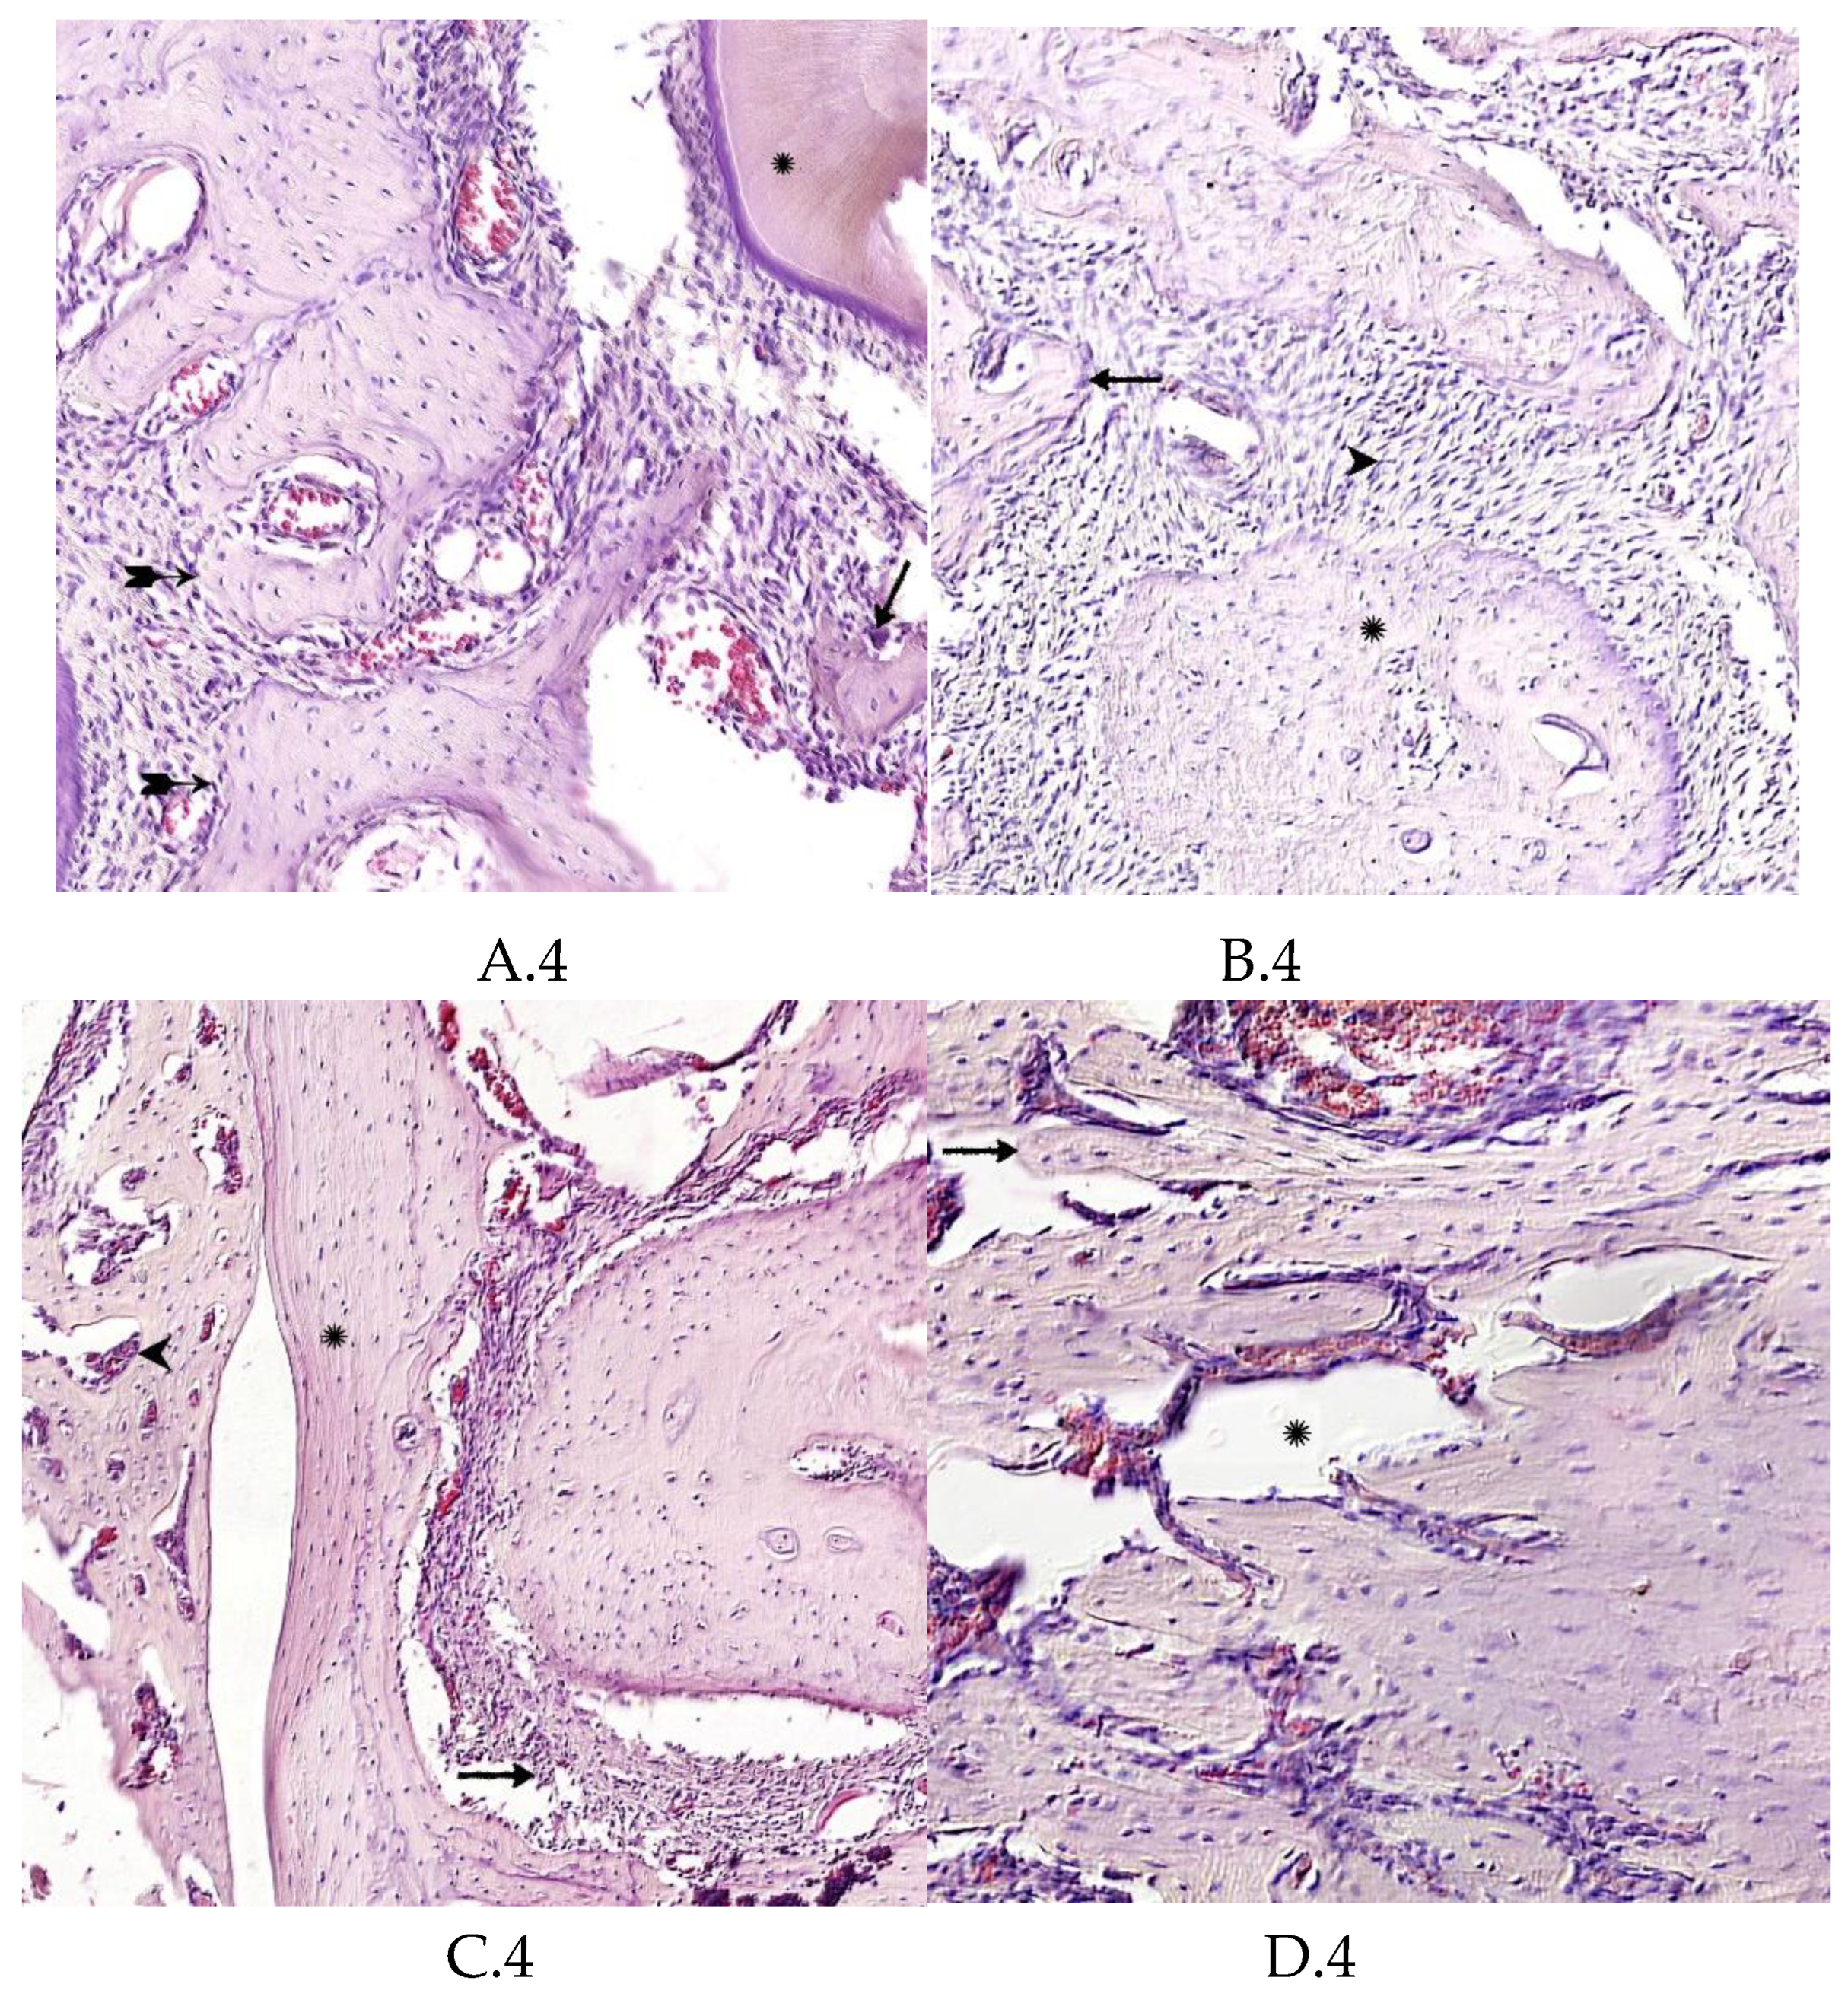

Morphological Analysis of Bone Tissue Restoration in the Defect Zone